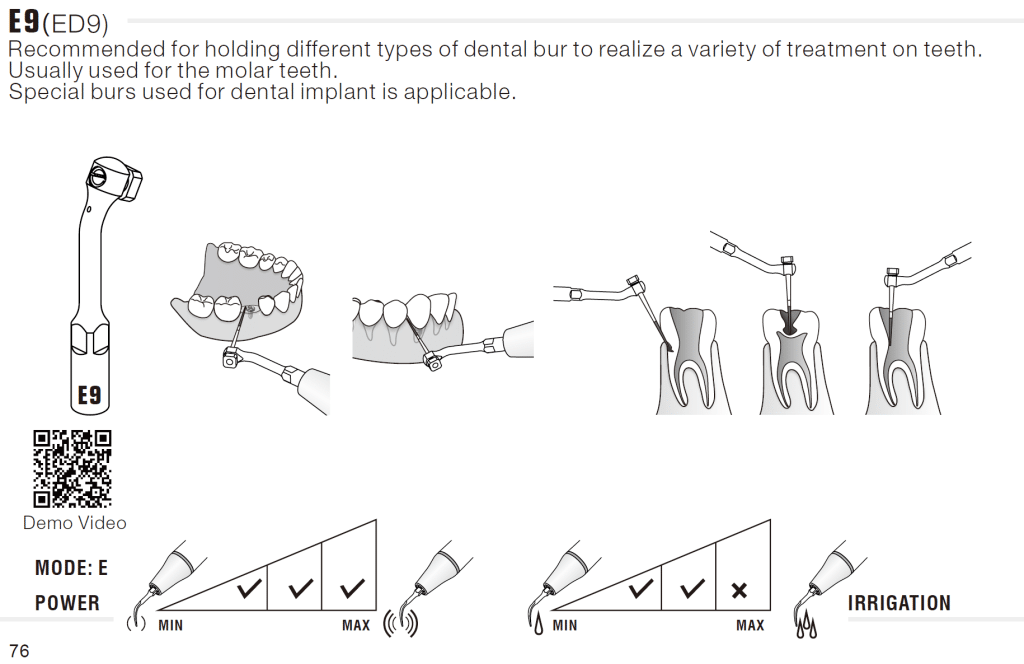

Ultrasonic preparation

Special Ultrasonic tip to remove excess cement